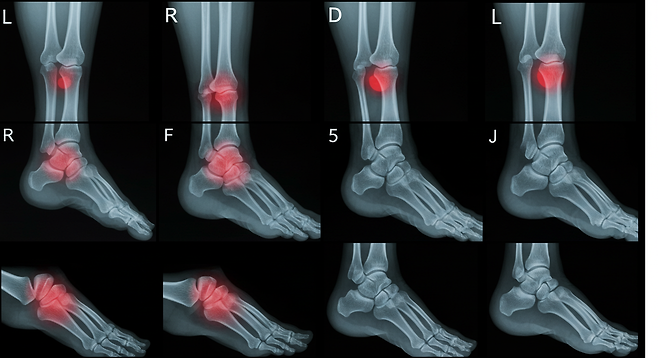

늑연골염은 주로 임상적 증상을 바탕으로 진단되며, 다른 심각한 원인을 배제하기 위해 심전도, X선, CT 또는 MRI 검사가 필요할 수 있습니다.